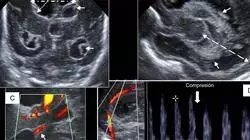

技术进步使得设备尺寸减小,有利于其降低成本和便携性,并且还提高了临床超声的功能,导致其应用显着增加。今天,您可以对许多儿科病理进行更精确的超声诊断,安全地进行超声引导干预,准确地对儿童进行非侵入性血流动力学评估,或快速评估任何类型的创伤。

• 超声影像专家介绍的临床病例进展

• 儿童超声诊断治疗的进展